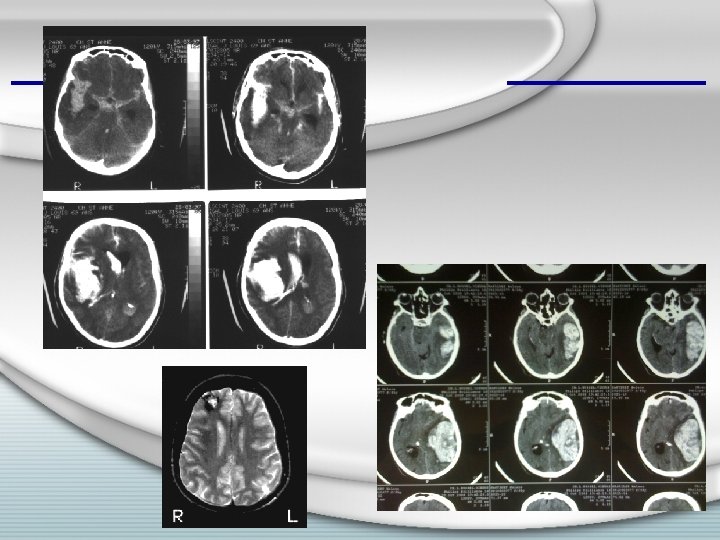

Imagerie • En urgence : – SCANNER cérébral – Sans injection • Collection intraparenchymateuse hyperdense • Effet de masse +/- œdème • Parfois : – Image surajoutée – Hydrocéphalie obstructive

Imagerie • En urgence, après le scanner, parfois : – Angiographie cérébrale – Angioscanner ou angio. IRM – IRM • Quand ? – – – Sujet jeune Pas d’HTA connue Topographie de l’hématome atypique Hétérogénéité de l’hyperdensité au scanner Hémorragie méningée associée / hématome en rapport avec le polygone de Willis / vallée sylvienne – Imagerie à refaire en différé parfois

• Exemple : f, 53 ans ; malaise brutal au domicile, tr vigilance et coma ; hémiplégie G, puis mydriase dte + décérébration G

• Exemple : f, 35 ans ; céphalées brutales, puis tr vigilance et déficit D, puis coma GCS= 6, hémiplégie D, sans signes d’engagement

• Exemple : f, 70 ans ; HTA ; malaise au domicile avec vertiges et vomissements, consciente , syndrome cérébelleux D